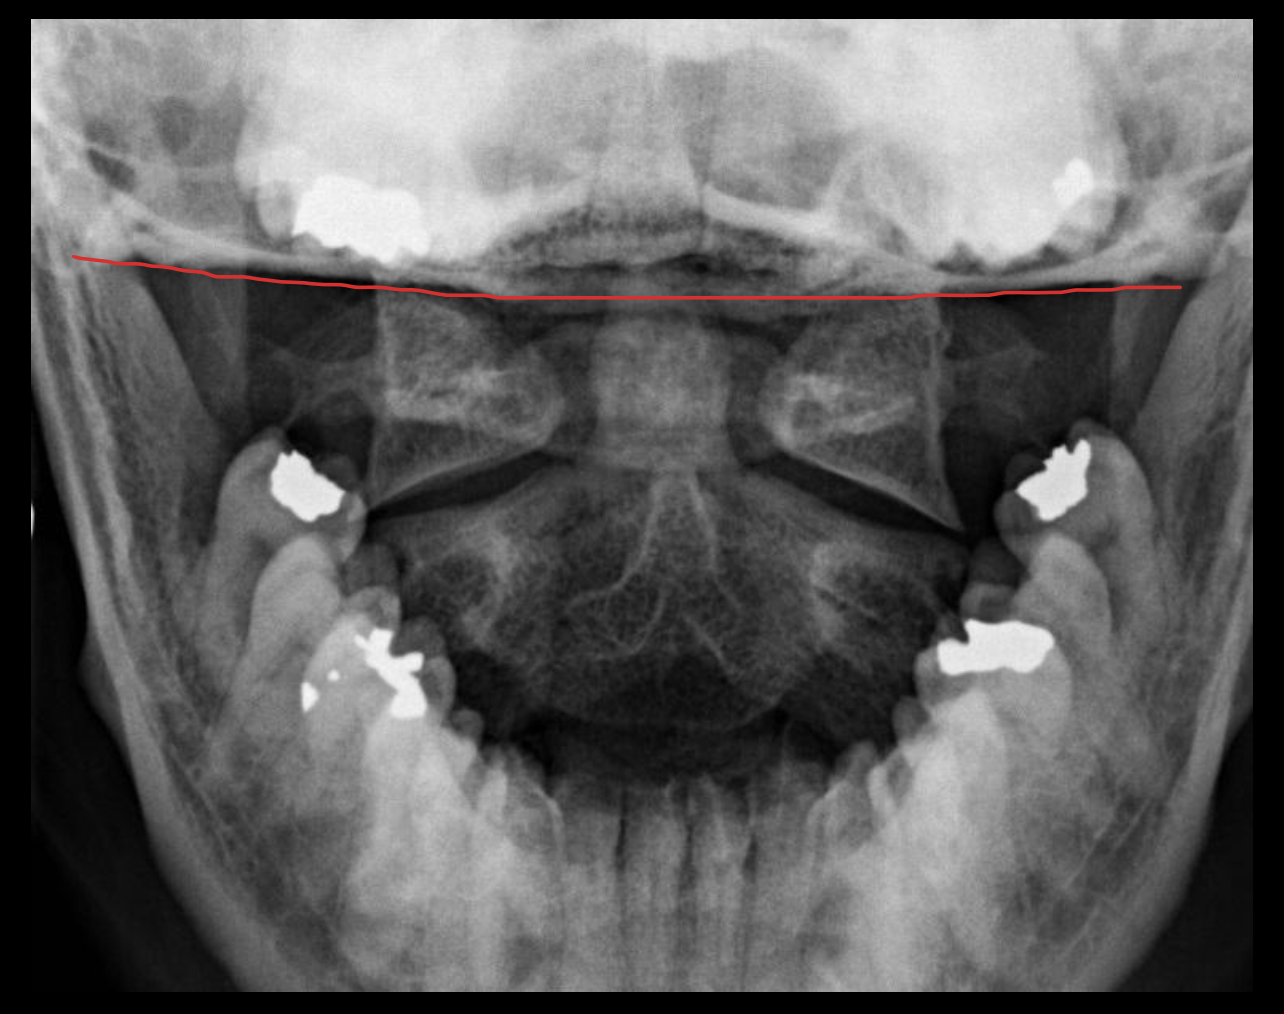

颅底

Base of skull

下颌骨

Mandible